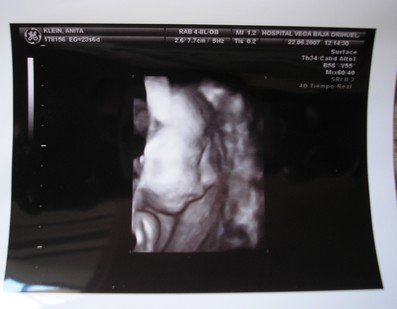

Ma kora reggel megszülettek a kicsi fiúk, róluk hoztam képeket nektek. Éjfél körül szivárgott a huginál a magzatvíz, felhívták a kórházat, ott mondták, inkább menjenek be, az a biztos. Kapott antibiotikumokat, de sajnos beindult a szülés. 4.32-kor megszületett a Bálint, 1990gr és 44cm, valmint 4.39-kor a Kristóf 2170gr és 44cm. Valami tüdősegítő oxigént kapnak, a Bálintnak sűrű volt a vére, de úgy néz ki, hogy helyre áll magától. Amint megindul a teje kiveheti őket szoptatni, talán 1 hetet kell bent lenni.

Kép

Ő a Kristóf.